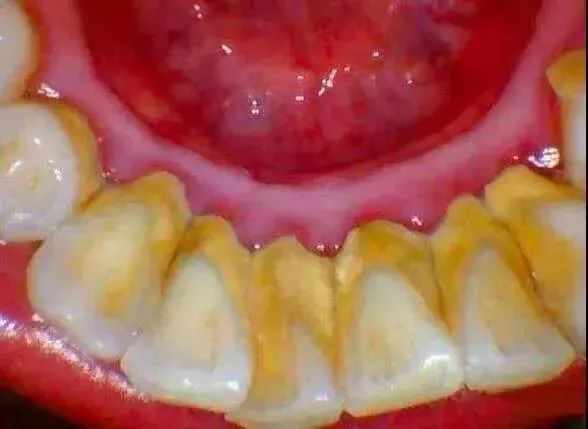

牙结石是附着在牙齿表面的硬性斑块,其外形似黄色干石灰块,较坚硬,易使牙龈出血。牙石上附着大量的菌斑。

牙结石

洗牙前后对比